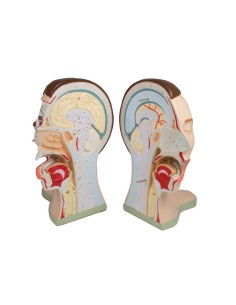

Scopri il Mondo dell’Anatomia con Modelli anatomici di Precisione

Dal cranio in 22 parti con incastri magnetici ai modelli di colonna vertebrale, da quelli di articolazioni a quelli di cuore, ogni pezzo della nostra collezione è progettato per un’immersione totale nello studio dell’anatomia umana. I nostri modelli, realizzati tramite scansioni di ossa vere, garantiscono un’esperienza tattile autentica e una fedeltà di peso quasi identica agli originali.

Essenziali per studenti e professionisti, i nostri modelli anatomici sono strumenti didattici che permettono di osservare le strutture anatomiche con precisione, eliminando la necessità di dissezioni o studi invasivi. Sono inoltre utili per spiegare ai pazienti le patologie, rendendo la comunicazione più efficace e risparmiando tempo prezioso.